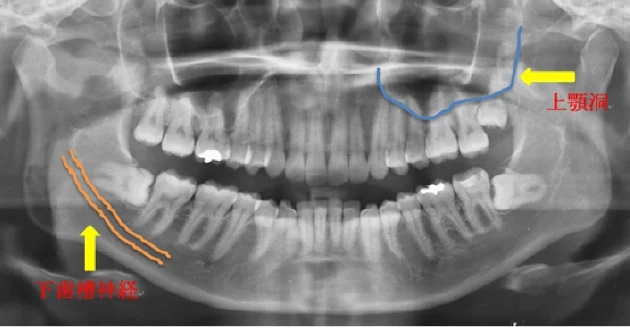

下顎には顔の感覚を司る神経が通っており、親知らずがこれらの神経に近いほど、圧迫や損傷の危険性が高まります。神経が損傷すると、唇などの部分に感覚麻痺が生じる可能性があり、完全に回復するまでに数ヶ月から数年かかることがあります。

上顎には上顎洞という空洞があり、抜歯により穿孔するリスクがあります。これにより、口内に空気が溜まったり、鼻から液体が漏れることがあります。

ii 抜歯下歯槽神経や上顎洞など、抜歯する歯の位置と周囲の重要な構造物との関係を慎重に分析した後、抜歯計画が出来上がりましたら歯を抜いていきます。